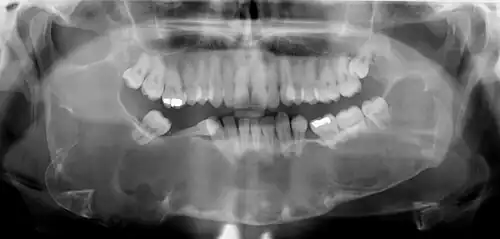

Classic look of an odontogenic keratocyst of the right mandible in the place of a former wisdom tooth. Well defined, unilocular, radiolucent lesion within the bone.

Radiographs of odontogenic keratocysts show well-defined radiolucent areas with rounded or scalloped margins which are well demarcated.[13] These areas can be multilocular or unilocular. The growth pattern of the lesion is very characteristic from which a diagnosis can be made as there is growth and spread both forward and backward along the medullary cavity with little expansion. No resorption of teeth or inferior dental canal and minimal displacement of teeth is seen. Due to lack of expansion of the odontogenic keratocyst, the lesion can be very large when radiographically discovered.[10]